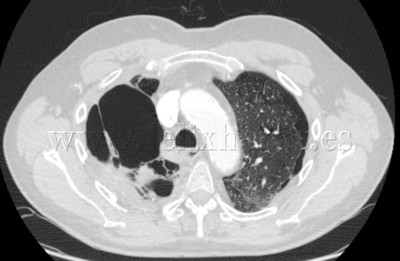

Enfisema pulmonar